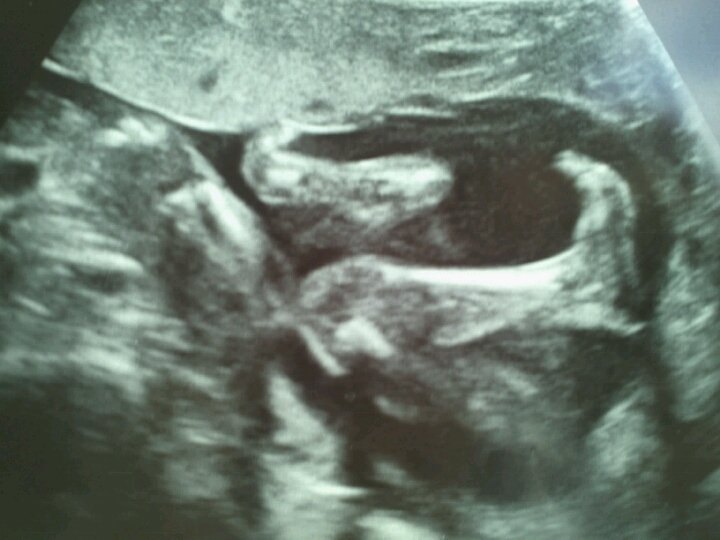

Alt så fint ud, det hele var som det skulle være. h*n lå og moslede rundt derinde, og kunne endda mærke det lige så tydeligt. det var så vildt. - far og mormor stod spændt og kiggede med, mens jeg lå og tudede til hjertelyd og små føder + spark og skub.

og sidst men ikke mindst... - VI SKAL HAVE EN PRINSESSE!  og hun skal hedde Sophia Regina. Regina er efter min bedste veninde som omkom i 2008, så det betyder virkelig ekstra meget for mig.

Fleeere piger! Tillykke med det dejlige resultat! Og sikke et skønt billede